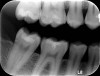

Fig 5. The 6-year radiograph confirmed the dentin bridge formation achieved with the tricalcium- and dicalcium-silicate material.

Figure 5